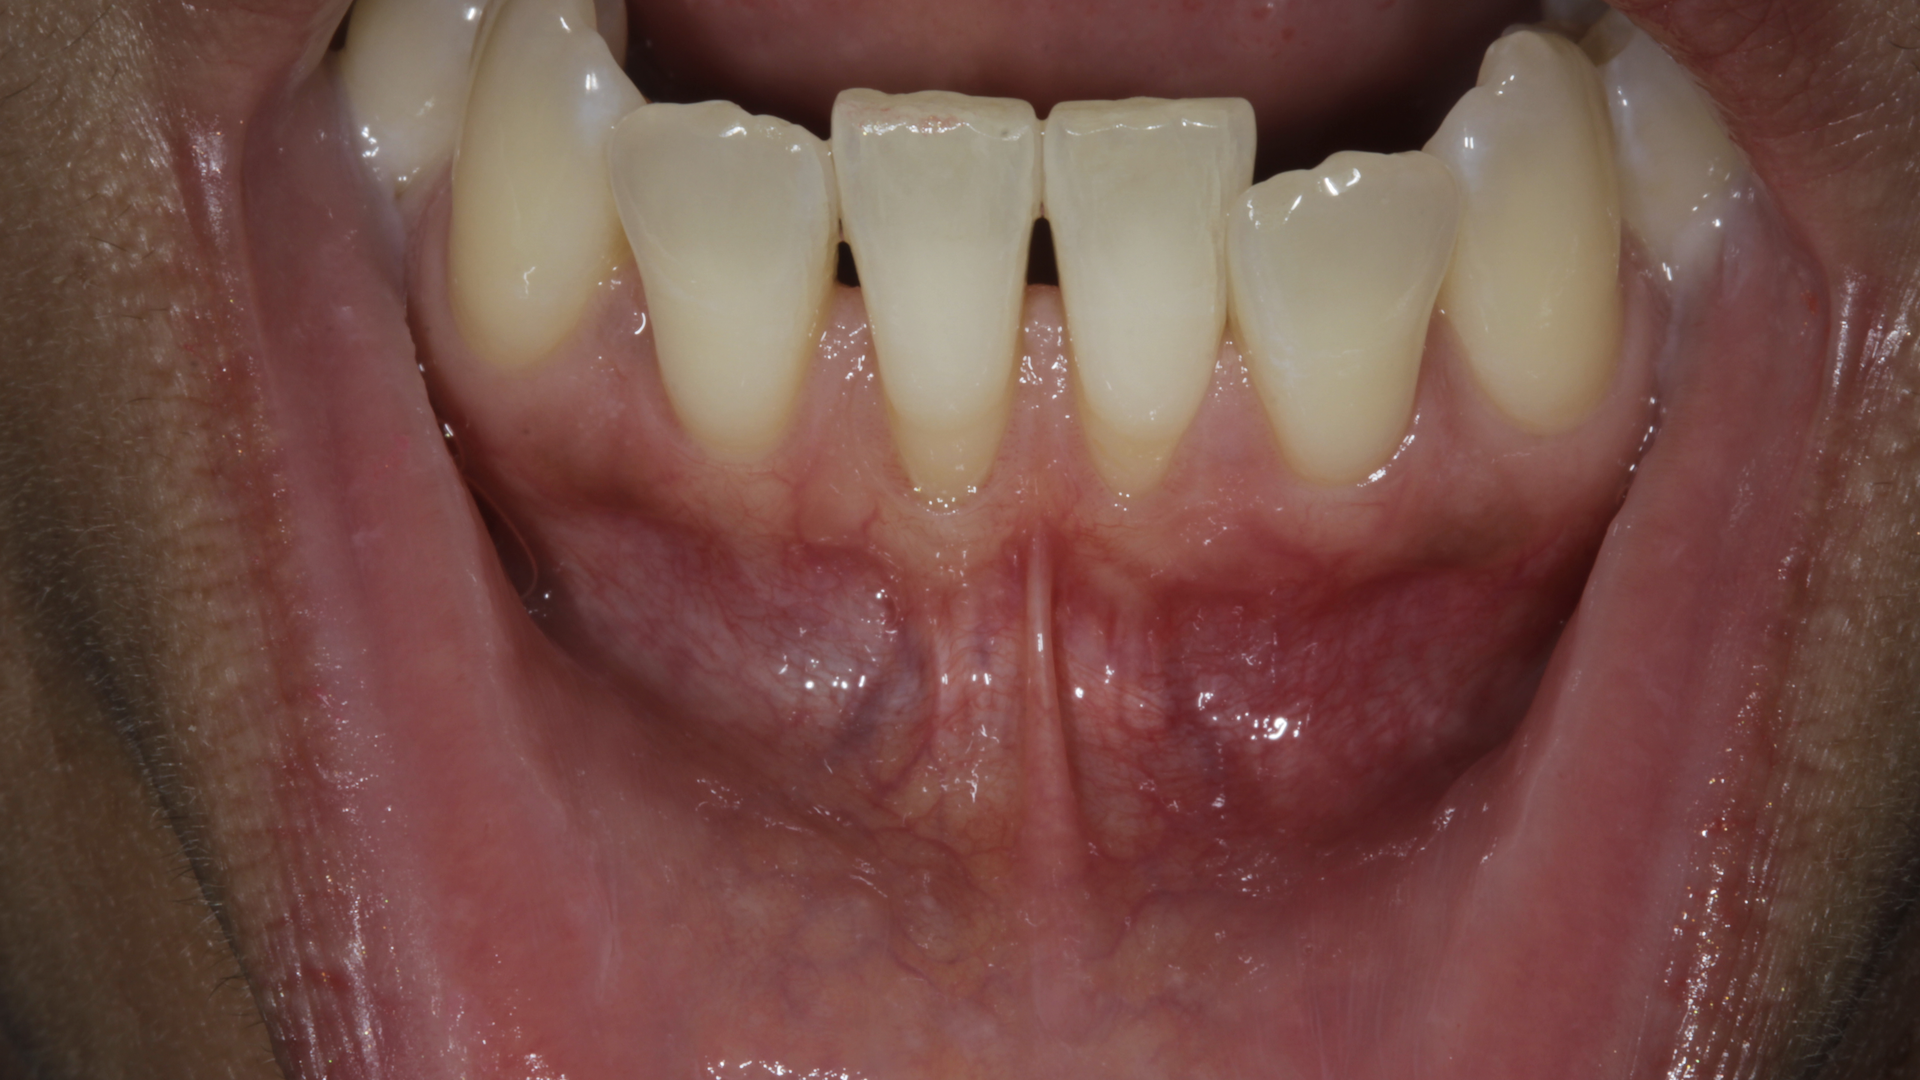

Current evidence regarding the treatment of gingival recession defects indicates that surgical therapeutic approaches are highly predictable for Miller class I and II single-tooth defects.1,11,12 A number of systematic reviews and randomized clinical trials have demonstrated the successful use of subepithelial connective tissue graft (SCTG) techniques when treating maxillofacial Miller class I and II single-tooth defects (figures 1 and 2). However, surgical challenges arise when patients present with Miller class III and IV defects, as well as multiple-tooth GR defects and linguopalatal mucogingival concerns (figures 3 and 4).1,11